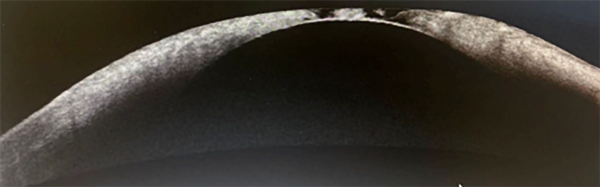

Se completó la exploración realizando una tomografía de coherencia óptica (OCT) de la córnea (fig. 2) que resultó de utilidad para registrar el adelgazamiento paracentral con pérdida de la arquitectura estromal y protrusión del endotelio, compatible con perforación inminente. Se tomaron muestras para descartar patógenos infecciosos y se inició tratamiento médico intensivo con colirios de vancomicina y ceftazidima alternados cada una hora, lubricantes con insulina, atropina al 1% y lubricación frecuente. Se indicó oclusión ocular entre las aplicaciones de gotas y reposo absoluto.

Figura 2. Tomografía de coherencia óptica de córnea donde se observa zona de adelgazamiento y afectación estructural a nivel central.

Figura 3. Alteración estromal con adelgazamiento corneal severo.